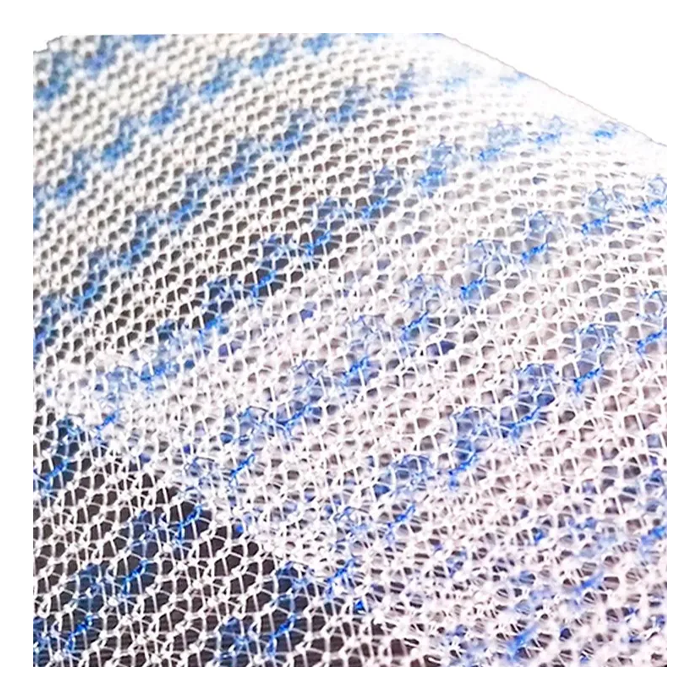

Эндопротез-сетка (сетка хирургическая) полипропиленовый для восстановительной хирургии ЭСФИЛ лёгкий, 8х12 см, Линтекс

Эндопротез-сетка полипропиленовая ЭСФИЛ лёгкий для восстановительной хирургии

Эндопротез-сетка ЭСФИЛ лёгкий от компании «Линтекс» — это современное и надежное решение для пластики грыж и восстановления целостности мягких тканей. Изделие представляет собой полипропиленовую сетку, специально разработанную для обеспечения прочной и долговечной поддержки в области хирургического вмешательства.

Ключевой особенностью данной модели является её «лёгкая» конструкция. Это означает, что сетка изготовлена из тонкого, но высокопрочного полипропиленового мононитяного материала с пониженной плотностью. Такой подход минимизирует количество имплантируемого инородного материала, что способствует лучшей интеграции с тканями организма и снижает риск послеоперационного дискомфорта для пациента.

- Оптимальная интеграция: Макропористая структура (размер пор более 1 мм) позволяет фибробластам и коллагеновым волокнам свободно прорастать через сетку, обеспечивая её надежное закрепление и естественное укрепление тканей.

| Тип плетения | Макропористая, монофиламентная сетка |

| Цвет | Белый / синий (для удобства ориентации на операционном поле) |